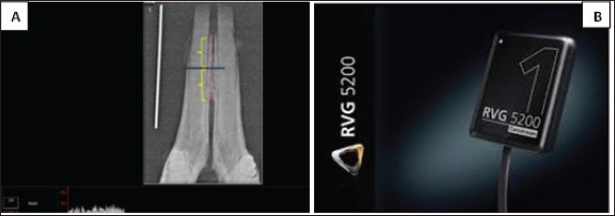

Digital radiographic assessment was performed using Carestream Imaging Software (v7.0.3) to evaluate bone density in the para-symphysis region of the right mandibular cancellous bone between the alveolar crest and bifurcation. Measurements were expressed in gray values (0–255 GV) and analyzed using standardized coronal and apical reference points (Pollard and Phillips, 2017). Radiographic recordings employed a size 1 dental digital sensor (RVG 5200, Carestream Dental LLC).

The jaw sample was placed on the sensor with its lingual part touching the sensor surface sleaved and the cone of the dental X-ray machine (Getidy intraoral X-ray system, tube). The source image distance was about 20 cm so that the central ray directed in perpendicular direction to sample surface which was parallel to sensor surface that in contact with it. Tube model K 127-0.8-70, settings were 70 kv and 7 mA with exposure time 0.30 as in Figure 5A and B. Radiographic bone density assessment is shown in Figure 4.

Fig. 4. (A): digital bone density assessment of target area of the rabbit mandibular jaw. (B): RVG 5,200 dental sensor (size 1); TROPHY,4, rue F. pelloutier, Croissy-Beabourg, 77,435 Marne La Vallee Cedex 2, France Carestream Dental LLC, Cumberland Boulevard, Suite 700, Atlanta, GA USA.